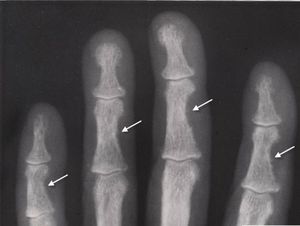

Hyperparathyroidisim

Peroisteal reaction in radical part of fingers ( in middle part )